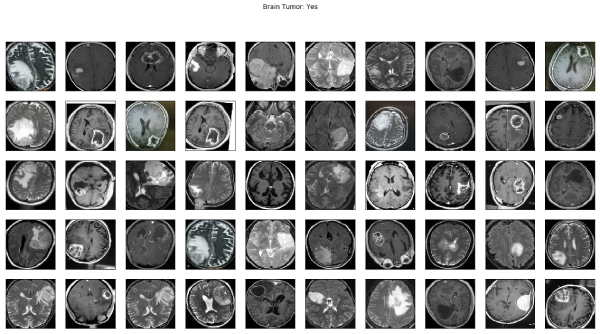

Brain Tumor Detection